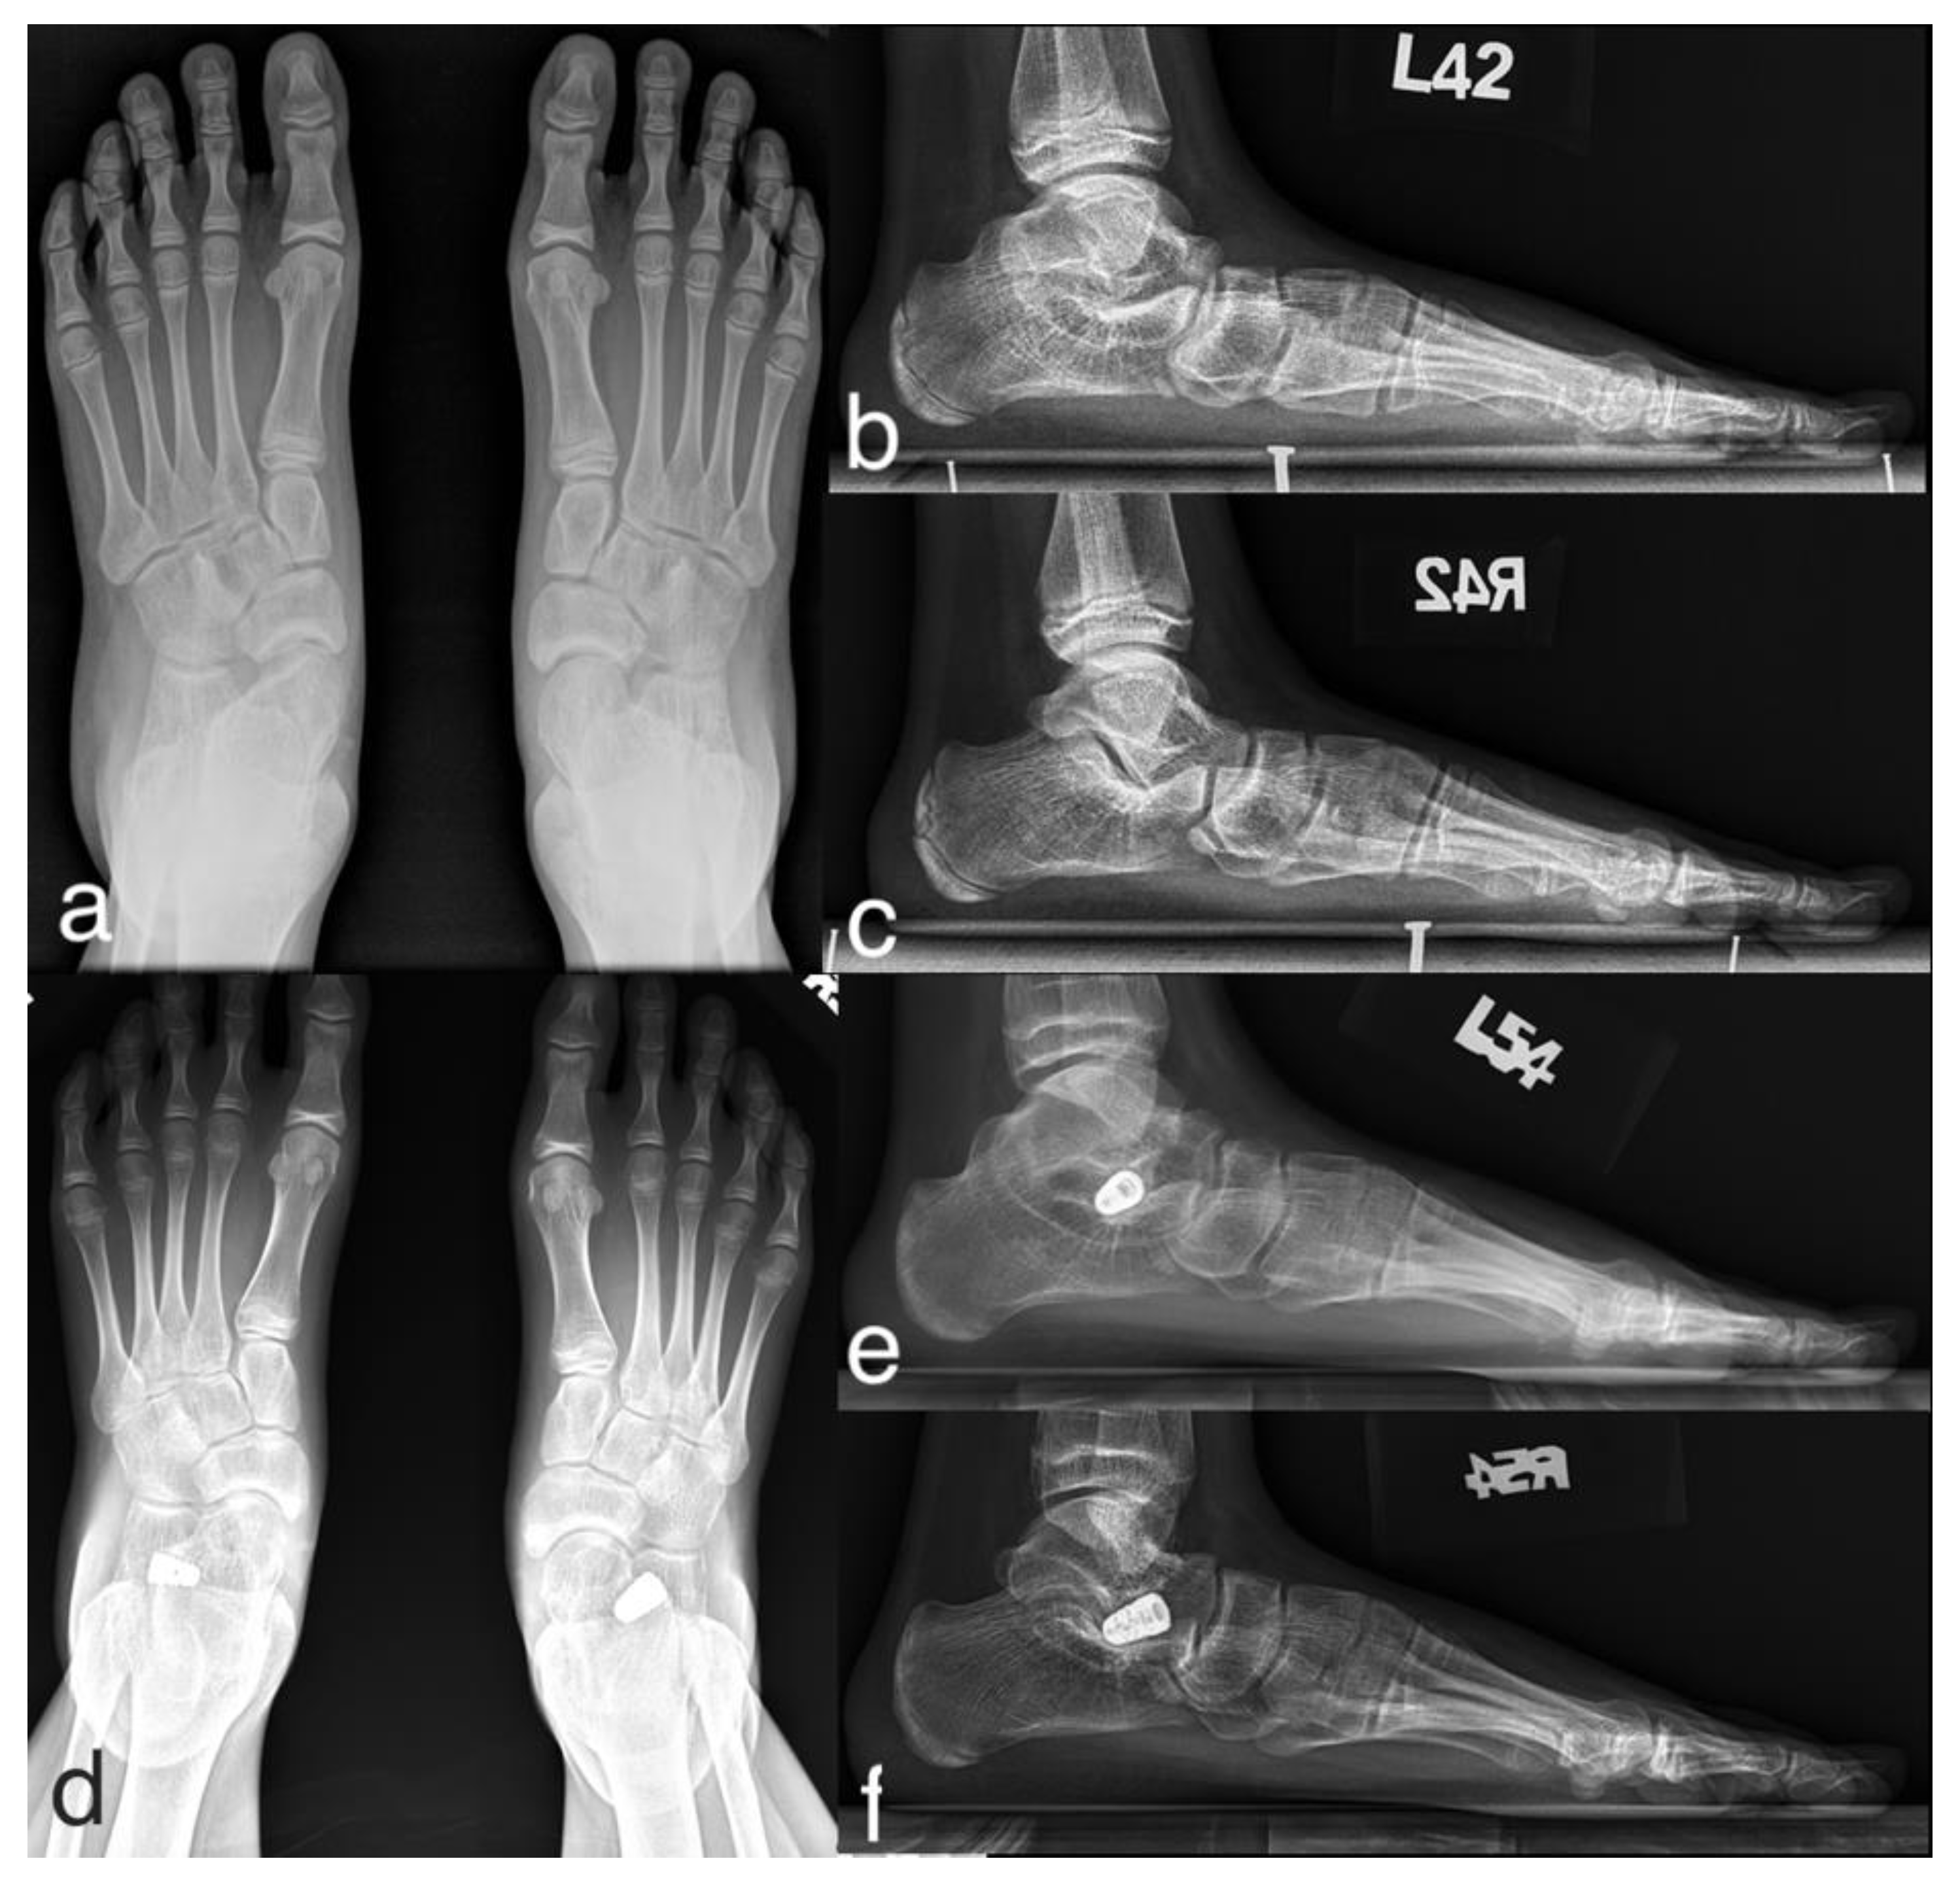

3.2. Case Presentation